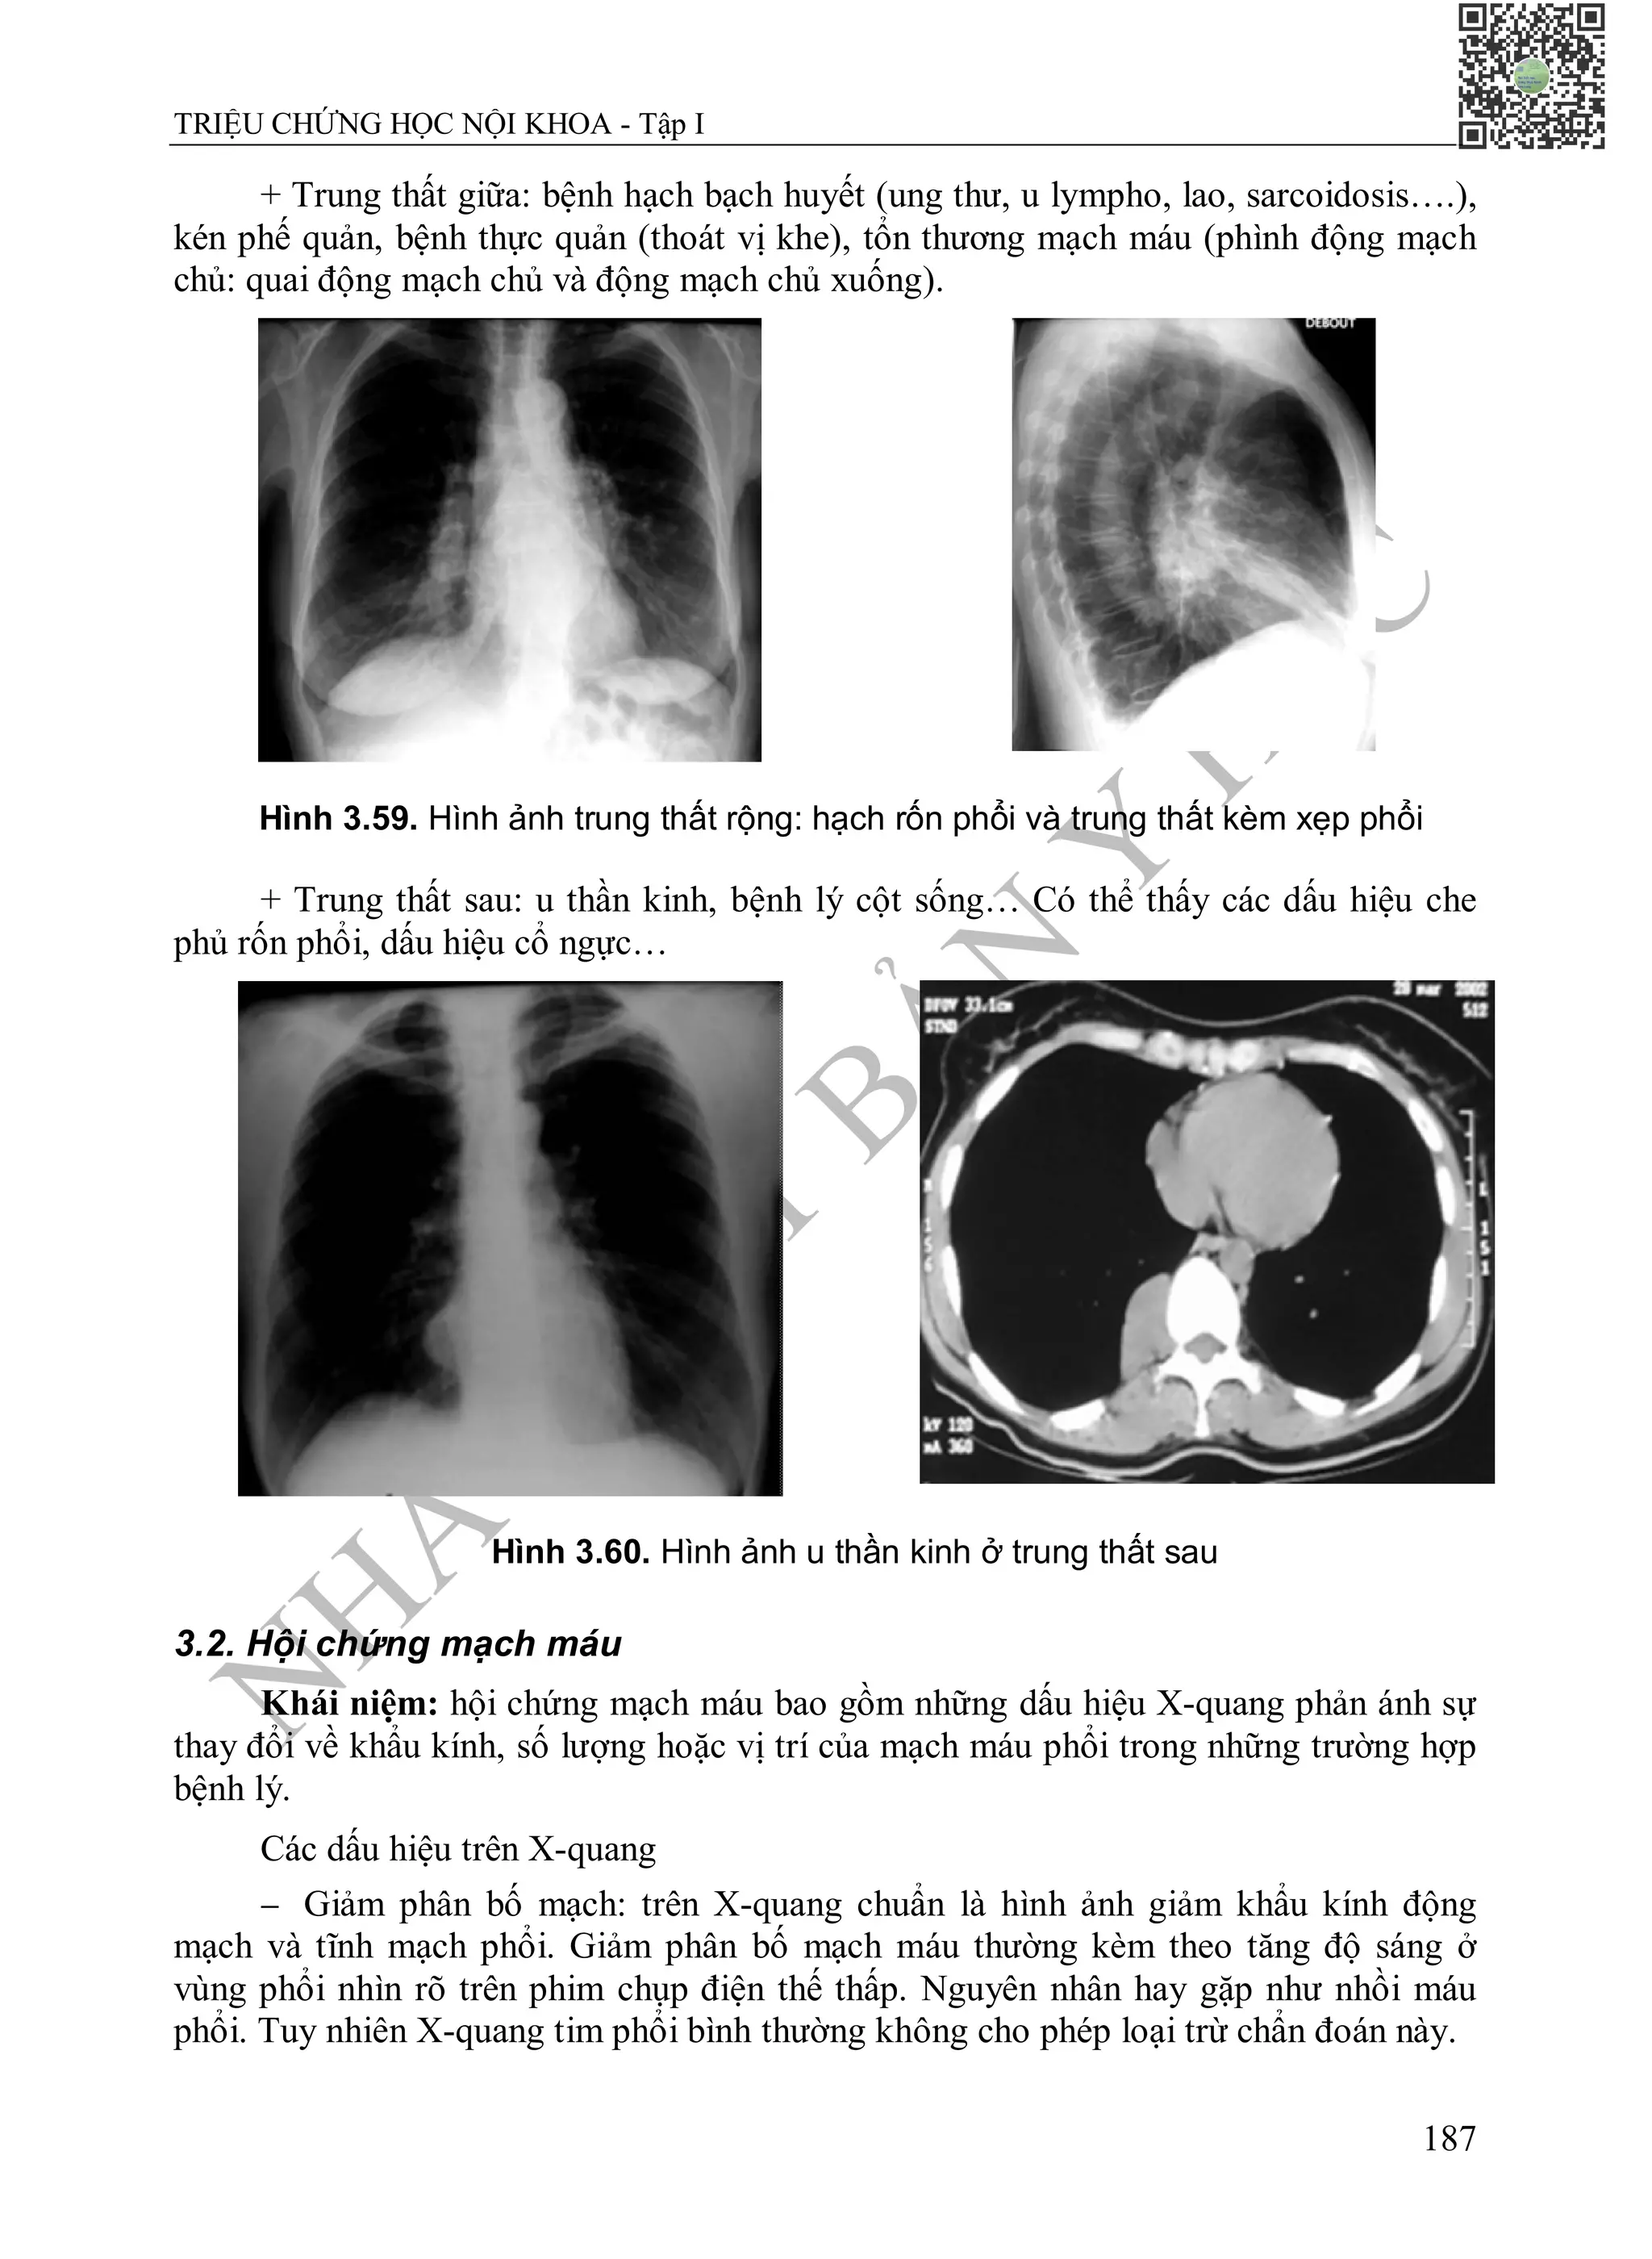

Sờ

 Xác định mỏm tim: là điểm đập thấp nhất và ngoài cùng nhất trên thành ngực,

thường ở trên vị trí giải phẫu thực sự của mỏm tim. Diện đập của tim to hơn và mỏm

tim xuống thấp hơn, sang trái, gặp trong trường hợp thất trái giãn.